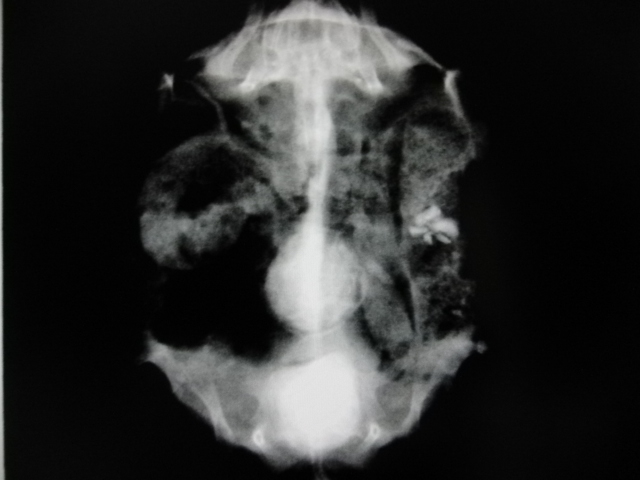

カメの中耳炎

エキゾチック

その他動物